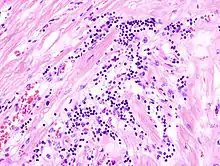

Virale Myokarditis

Ät.: Coxsackie-, ECHO-, Adenoviren, Influenzaviren

Pathogenese: Herzmuskelnekrose durch Virus und T-Zell-vermittelte Immunreaktion.

Mikro: Interstitielles lymphozytäres Infiltrat (kleine blaue Zellen), kaum Nekrosen.

![]() Virale Myokarditis bei Patient mit plötzlichem kongestiven Herzversagen, Autopsiepräparat, H&E. |

![]() idem. |